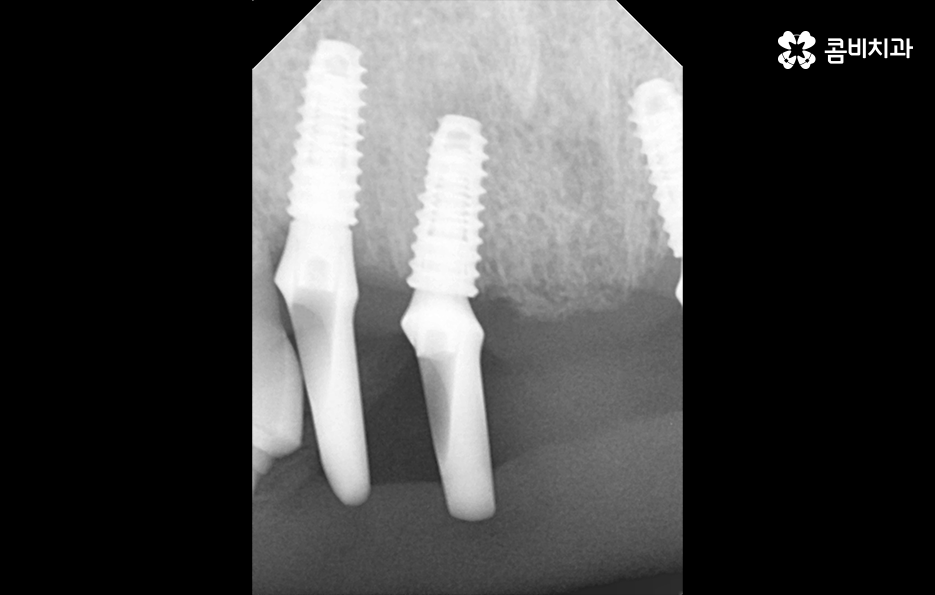

오늘 포스팅의 사례의 경우 앞니를 이미 잃은 상태였지만 주변 치아를 활용하여 브릿지로 연결해놓은 상태에서 기존의 치아가 버티지 못하여 앞니임플란트 하게 된 경우라고 볼 수 있는데요.

일반적으로 앞니임플란트의 경우 원데이임플란트라고 불리는 치아를 발치 후 즉시 임플란트를 식립하는 방법으로 치료하는 경우가 많은데 그 이유는 앞니의 특성상 심미적으로 중요하기 때문에 빠른 치료를 통해 임시치아를 부착하여 심미적 부담감을 줄일 수 있고 잇몸 라인을 살리는데 원데이 임플란트 방식이 유리한 부분도 있어요

잇몸 상태와 전신 건강이 양호한 경우에는 원데이임플란트를 통해 앞니임플란트 치료를 많이 진행하지만 오늘 케이스처럼 이미 치아를 발치한 후 시간이 지난 경우나 치주염으로 인해 잇몸 뼈가 녹고 염증이 심한 경우에는 빠른 치료보다는 잇몸을 충분히 회복하여 건강하고 안전한 결과에 더 초점을 두고 있는데요.